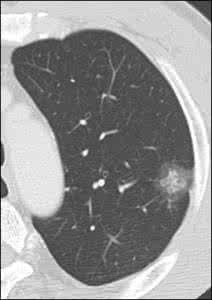

淺表的結節可以通過觸診進行診斷,再深的結節需要通過超聲、X光機、CT、磁共振等進行診斷。不同的診斷方式可以診斷的器官和組織不同,即使相同器官和組織的不同性質的實性結節,不同的診斷方式的敏感性也不同。

對於實性結節的診斷,一般而言,其良惡性的診斷最為重要。不同器官和組織的不同性質的結節,其嚴重程度不同,臨床處理手段也不同。